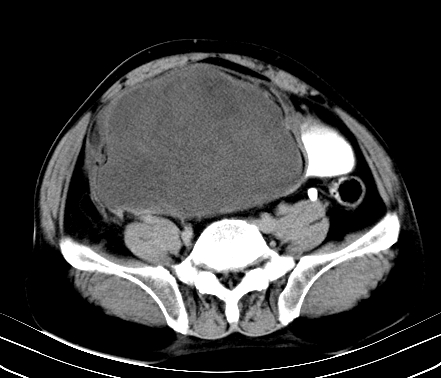

标题: CT19729B:男,74岁,因腿疼就诊,查体触腹部肿物,

增强扫描

静脉期

【ct表现】

1、肿块巨大,往往位于腹膜后,长大后才引起症状而就诊;那么位于腹膜后的肿瘤80%为恶性肿瘤。

2、实性肿瘤,增强扫描轻度不均强化,实性肿瘤一般不是好东西。

3、肿瘤边缘似见少许脂肪样密度。

4、腹膜后未见肿大淋巴结,但肿瘤于临近的肠管及组织接触紧密。

【诊断】

腹部占位,考虑位于腹膜后的恶性肿瘤,脂肪肉瘤(实体型)可能性大。

术后病理结果:腹膜后脂肪肉瘤。